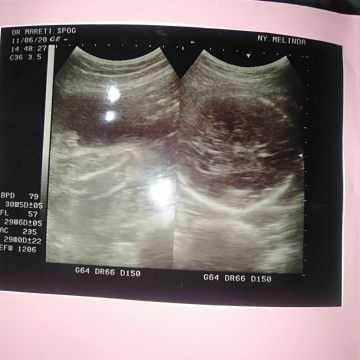

Ini bunda yang lebih jelas ny lagi tolong bacain ya bunda hpl SMA GA (usia kandungan)

Bun tolong SH bacain hasil USG saya..emang SH udh agak lama USG ny..masih bingung cara baca ny..cma pengan tau hpl SMA GA( usia kandungan/janin)